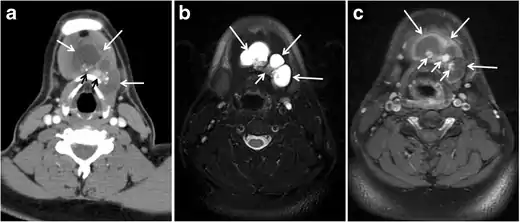

Fig. 9. A 58-year-old male patient with persistence PTC at thyroid bed with hypervascular nodal metastasis. a–c Transverse greyscale and colour Doppler neck ultrasound demonstrate hypoehoic soft tissue in the left thyroid bed (white arrow in a). There are a heterogeneous enlarged lymph nodes at level 2 and 3 with markedly increased vascularity (white arrow in b and c). d–f Enhanced axial CT images of the neck demonstrate a 2.7 × 1.4 cm hypodense soft tissue lesion anterior to the left carotid sheath (white arrow). There are left-sided enhancing abnormal and enlarged lymph nodes at cervical level 2 and 3 (black arrows).[1]

Fig. 11. Thyroid non-Hodgkin's large B-cell lymphoma in a 66-year-old female patient. an Axial enhanced neck CT scan demonstrates left thyroid lobe and isthmus homogeneously hypodense and minimally enhancing mass (white arrows). This lesion invades the prevertebral muscles (black arrows). Note the multiple enlarged level V lymph nodes (white arrowheads). b Post-treatment image shows significant reduction in size and mass effect of the left thyroid infiltrative mass, with almost complete resolution of the left cervical lymphadenopathy.[1]

Fig. 12. Diffuse thyroid large B-cell lymphoma in a 79-year-old female patient. an Axial enhanced neck CT scan demonstrates a homogeneously hypodense and minimally enhancing large right thyroid solid mass (long white arrow) extending into the thyroid isthmus. It is encasing the right carotid artery (short white arrow) and displacing of the trachea and oesophagus to the left side.[1]